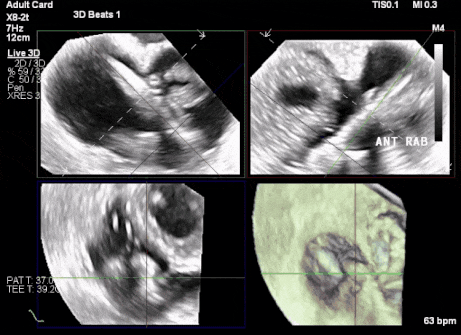

術后超聲顯示人工瓣膜穩(wěn)定性良好,瓣葉啟閉正常

術前超聲顯示三尖瓣重度反流合并拴系

術中TEE成像困難,偽影干擾

術后DSA、超聲顯示人工瓣膜穩(wěn)定性良好,瓣葉啟閉正常,無瓣周漏